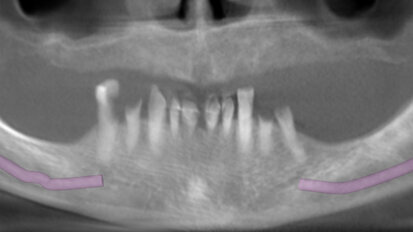

Atraumatic extraction of maxillary first premolar

A 70-year-old female patient visited our clinic owing to a fractured maxillary first molar. Tooth #24 had previously had a large composite restoration that ...